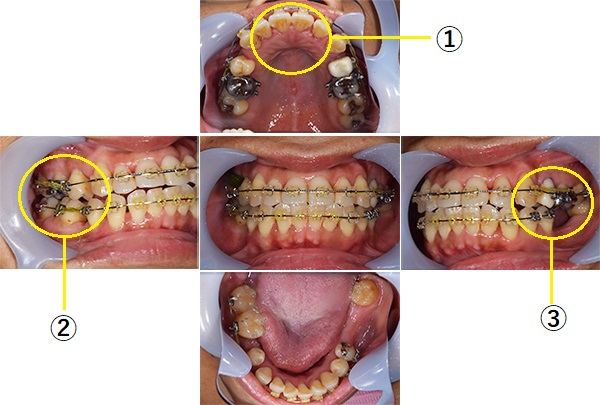

左右上下合わせて4本の抜歯を行った

①前歯もキレイに並んできました

②上の歯が外側になり、交叉咬合がなくなりました

③左上の出ていた歯を元の位置までもどしています